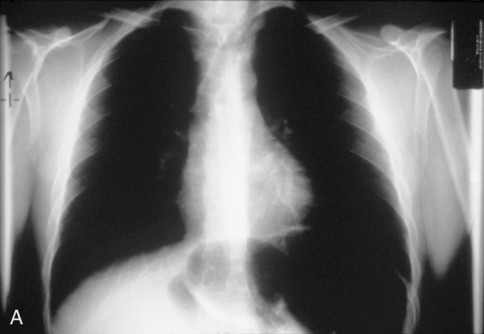

- Chest radiograph if suspect cancer:

- Chest radiograph showing airway deviation → axial CT or MRI